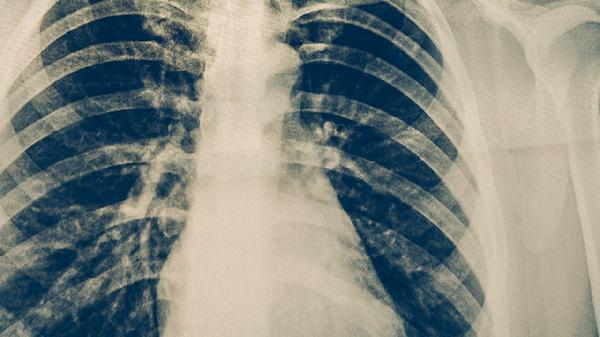

結核病密切接觸者、HIV感染者、糖尿病患者等高風險人群應每年進行胸部X線或結核菌素試驗檢查。出現(xiàn)咳嗽咳痰超過2周、低熱盜汗等可疑癥狀時,需及時進行痰涂片和GeneXpert檢測。潛伏結核感染者可在醫(yī)生指導下預防性服用異煙肼。